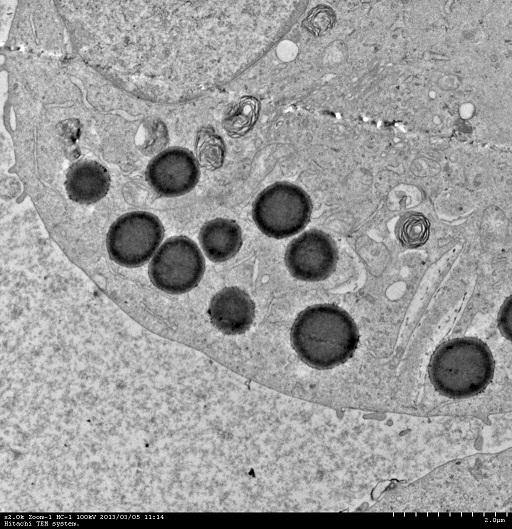

我自己养的A549细胞,总是出现这些黑色的大点,1微米左右,是不是支原体污染呀,怎么消除,大神,来帮帮我吧!!!!!

貌似细胞要发生调亡时出现的过氧化物颗粒,或则是一些包含大量脂类的颗粒!